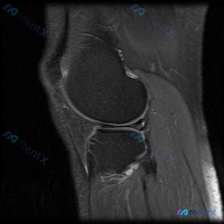

这是一张膝关节MRI矢状位单层面影像,临床疑问是:是否存在半月板异常?

- 半月板:本次层面显示的半月板呈典型三角形低信号,结构连续,没有看到异常高信号贯穿半月板,形态基本正常

最明显的异常在胫骨平台后侧、膝关节后间隙及腘窝区域:可以看到边界清晰的团块状/囊袋状局限性高信号,信号和关节液一致,属于典型的液性积聚表现。

结合现有信息,最可能的首先考虑是腘窝囊肿(Baker囊肿),合并不同程度的关节积液;半月板在本次观察层面没有明确异常,但不能排除存在隐匿性半月板病变作为囊肿/积液的原发病因。